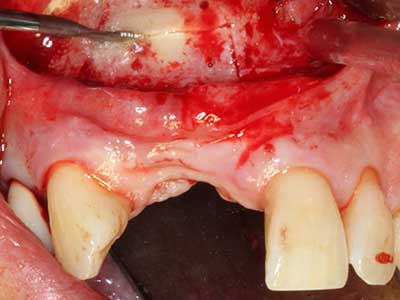

Fig. 13: Adequate irrigation with the 4-mm residual bone width is essential for this 52-year-old patient during the bone splitting.

Piezo surgery has additional advantages when harvesting bone blocks. In addition to the high precision with osteotomy described above, the use of the thin saw tips specifically minimizes loss of material. Greater loss of material during harvesting can be expected with the thicker instrument tips, particularly when using Lindemann drills (Lakshmiganthan, Gokulanathan et al. 2012). The basal separation, which is necessary particularly for retromolar block transplants, is simplified by specially designed rectangular saws, with the result that piezo surgery is viewed as a precise, simple and safe procedure for harvesting retromolar bone blocks (Happe 2007) (Fig. 1-12).

Indication: Bone splitting

Bone tissue is not simply a mineral structure but also contains a substantial proportion of collagen fibres. This means it not only has good compressive strength but also a degree of flexibility, which can be taken advantage of when performing bone augmentations. In the classical expansion procedure using bone splitting, the atrophied alveolar ridge is split longitudinally and carefully expanded after reaching an adequate osteotomy depth (Fig. 13-16), ideally without substantial removal of the periosteum (Brugnami, Caiazzo et al. 2014, Stricker, Fleiner et al. 2014). Screw and plate systems with increasing expansion distance have proven effective in separating the two bone lamellae while remaining below the fracture threshold. In general, residual bone widths of at least 3–4 mm are required (Chiapasco, Zaniboni et al. 2006) to guarantee adequate flexibility and sufficient bone coverage of the future implants. If necessary, a vertical relief osteotomy on one or both sides can improve flexibility. A combination with additional augmentation techniques, particularly on the buccal side, has been described as an alternative to the classical technique.

The splitting procedure is particularly atraumatic and there is no significant loss of dimension when using piezosaws, and there are no significant differences between implants in split jaws and implants in an alveolar ridge without a bone deficit (Chiapasco, Zaniboni et al. 2006, Danza, Guidi et al. 2009). However, sufficient continuous irrigation is essential, particularly with locally restricted and deep splitting to prevent thermal stress in the apical osteotomy regions.